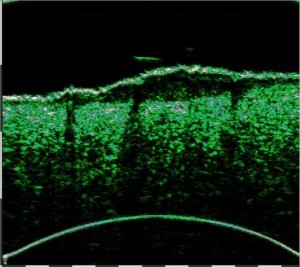

-Υπέρηχος Υψηλής Συχνότητας (HFUS) και Ιστολογία

Εφαρμογές δερματολογίας

-Κύριες εφαρμογές

-Κύριες παθολογικές διεργασίες